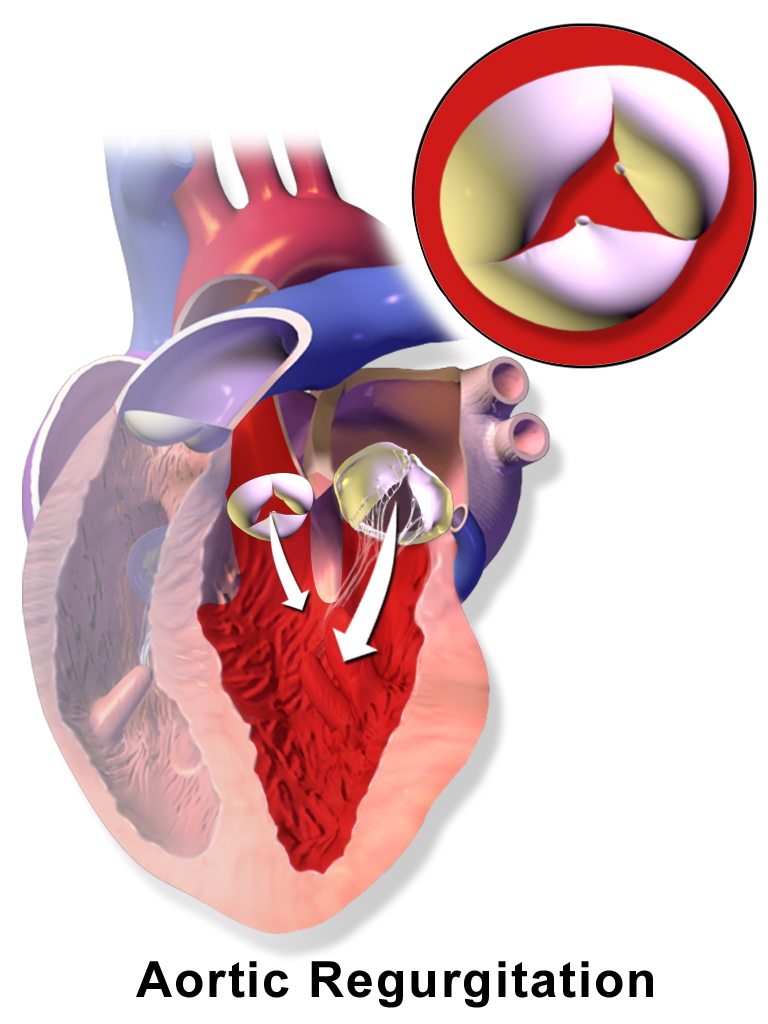

Aortic Regurgitation

Aortic regurgitation is the backflow of blood from the aorta into the left ventricle during diastole caused by aortic root dilatation or valve damage.

Aortic regurgitation is the most common cause of isolated aortic root dilation.

Clinical features of aortic regurgitation include an early, blowing diastolic murmur and hyperdynamic circulation due to increased pulse pressure.

The difference between systolic and diastolic pressures is known as pulse pressure.

Diastolic pressure decreases as a result of regurgitation, but systolic pressure increases as a result of increased stroke volume.

The increased pulse pressure associated with aortic regurgitation is characterized by:

- Water-hammer pulse

- Pulsating nail bed also known as the Quincke pulse

- Head bobbing

Aortic regurgitation results in left ventricle dilation and eccentric hypertrophy due to volume overload.

Treatment of aortic regurgitation is valve replacement once left ventricle dysfunction develops.